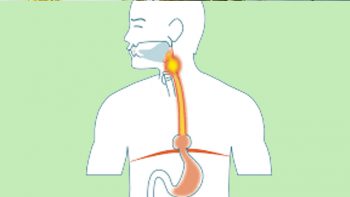

പ്രധാനമായും ശ്വാസനാളങ്ങളുടെ വീക്കം (Airway remodelling) ദീര്ഘകാല അടിസ്ഥാനത്തില് ശ്വസനം കൂടുതല് ബുദ്ധിമുട്ടിലാക്കുന്നു. ആസ്തമ നിയന്ത്രണ വിധേയമല്ലാത്ത ആളുകളില് ഇടയ്ക്കിടെ ശ്വാസകോശ സംബന്ധമായ അസുഖങ്ങളാല് ആശുപത്രി സന്ദര്ശനം വേണ്ടി വന്നേക്കാം. അതുപോലെതന്നെ ശ്വാസകോശത്തിന്റെ പ്രവര്ത്തനം കുറയാനും സാധ്യത കൂടുതലാണ്.

ദീര്ഘകാല ആസ്തമ ദൈനംദിന പ്രവര്ത്തനങ്ങളെ- ജോലി, ഉറക്കം, വ്യായാമം- എന്നിവയെ പ്രതികൂലമായി ബാധിച്ചേക്കാം. അപൂര്വ സന്ദര്ഭങ്ങളില് ചികിത്സയോടു പ്രതികരിക്കാത്ത ആസ്ത്മ ആവര്ത്തിച്ചുള്ള അണുബാധകള് അല്ലെങ്കില് ശ്വസനപരാജയം തുടങ്ങിയ ഗുരുതര സങ്കീര്ണതകളിലേക്ക് നയിച്ചേക്കാം. ശരിയായ ഇന്ഹേലർ ഉപയോഗത്തിലൂടെയും അതിനോടൊപ്പംതന്നെ ആസ്ത്മ രോഗത്തിന്റെ പ്രേരണ ഘടകങ്ങള് മനസിലാക്കി അവ ഒഴിവാക്കിയും രോഗലക്ഷണങ്ങള് ഒരു പരിധിവരെ നിയന്ത്രിക്കാം.